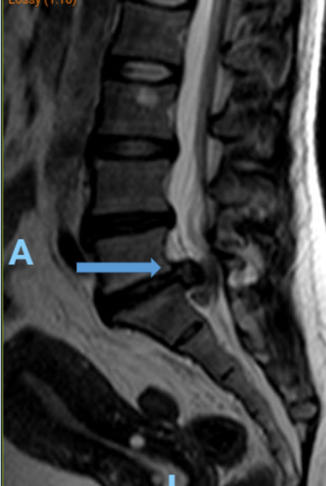

Hernia de disco lumbar extrusa L5 S1 (cortes

sagital y coronal en resonancia magnética)

Hernia de disco lumbar extrusa L5 S1 (cortes sagital y coronal en resonancia magnética)